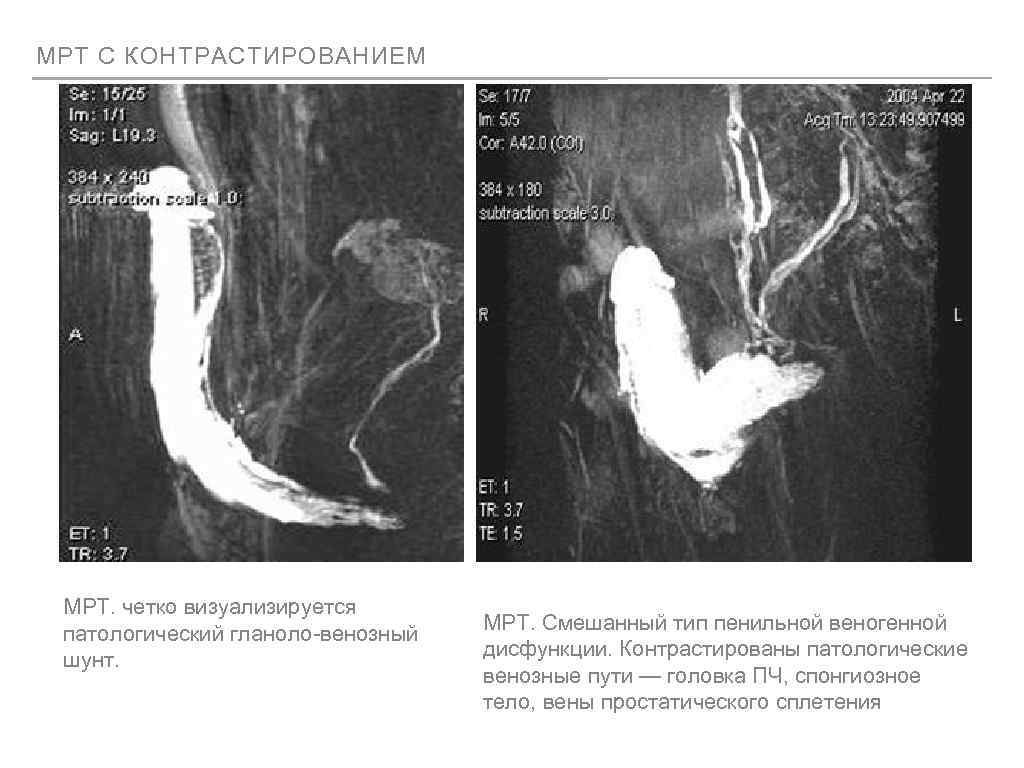

МРТ С КОНТРАСТИРОВАНИЕМ МРТ. четко визуализируется патологический гланоло-венозный шунт. МРТ. Смешанный тип пенильной веногенной дисфункции. Контрастированы патологические венозные пути — головка ПЧ, спонгиозное тело, вены простатического сплетения